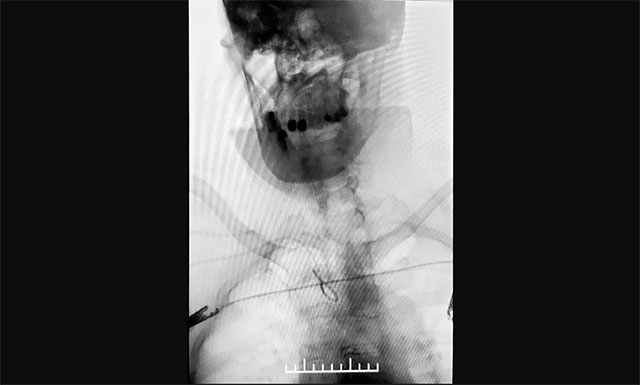

與傳統(tǒng)經(jīng)股動(dòng)脈穿刺腦血管造影相比,經(jīng)橈動(dòng)脈穿刺造影相對(duì)復(fù)雜,但手術(shù)創(chuàng)傷小、穿刺點(diǎn)血腫發(fā)生率較低

▲ 與傳統(tǒng)經(jīng)股動(dòng)脈穿刺腦血管造影相比,經(jīng)橈動(dòng)脈穿刺造影相對(duì)復(fù)雜,但手術(shù)創(chuàng)傷小、穿刺點(diǎn)血腫發(fā)生率較低